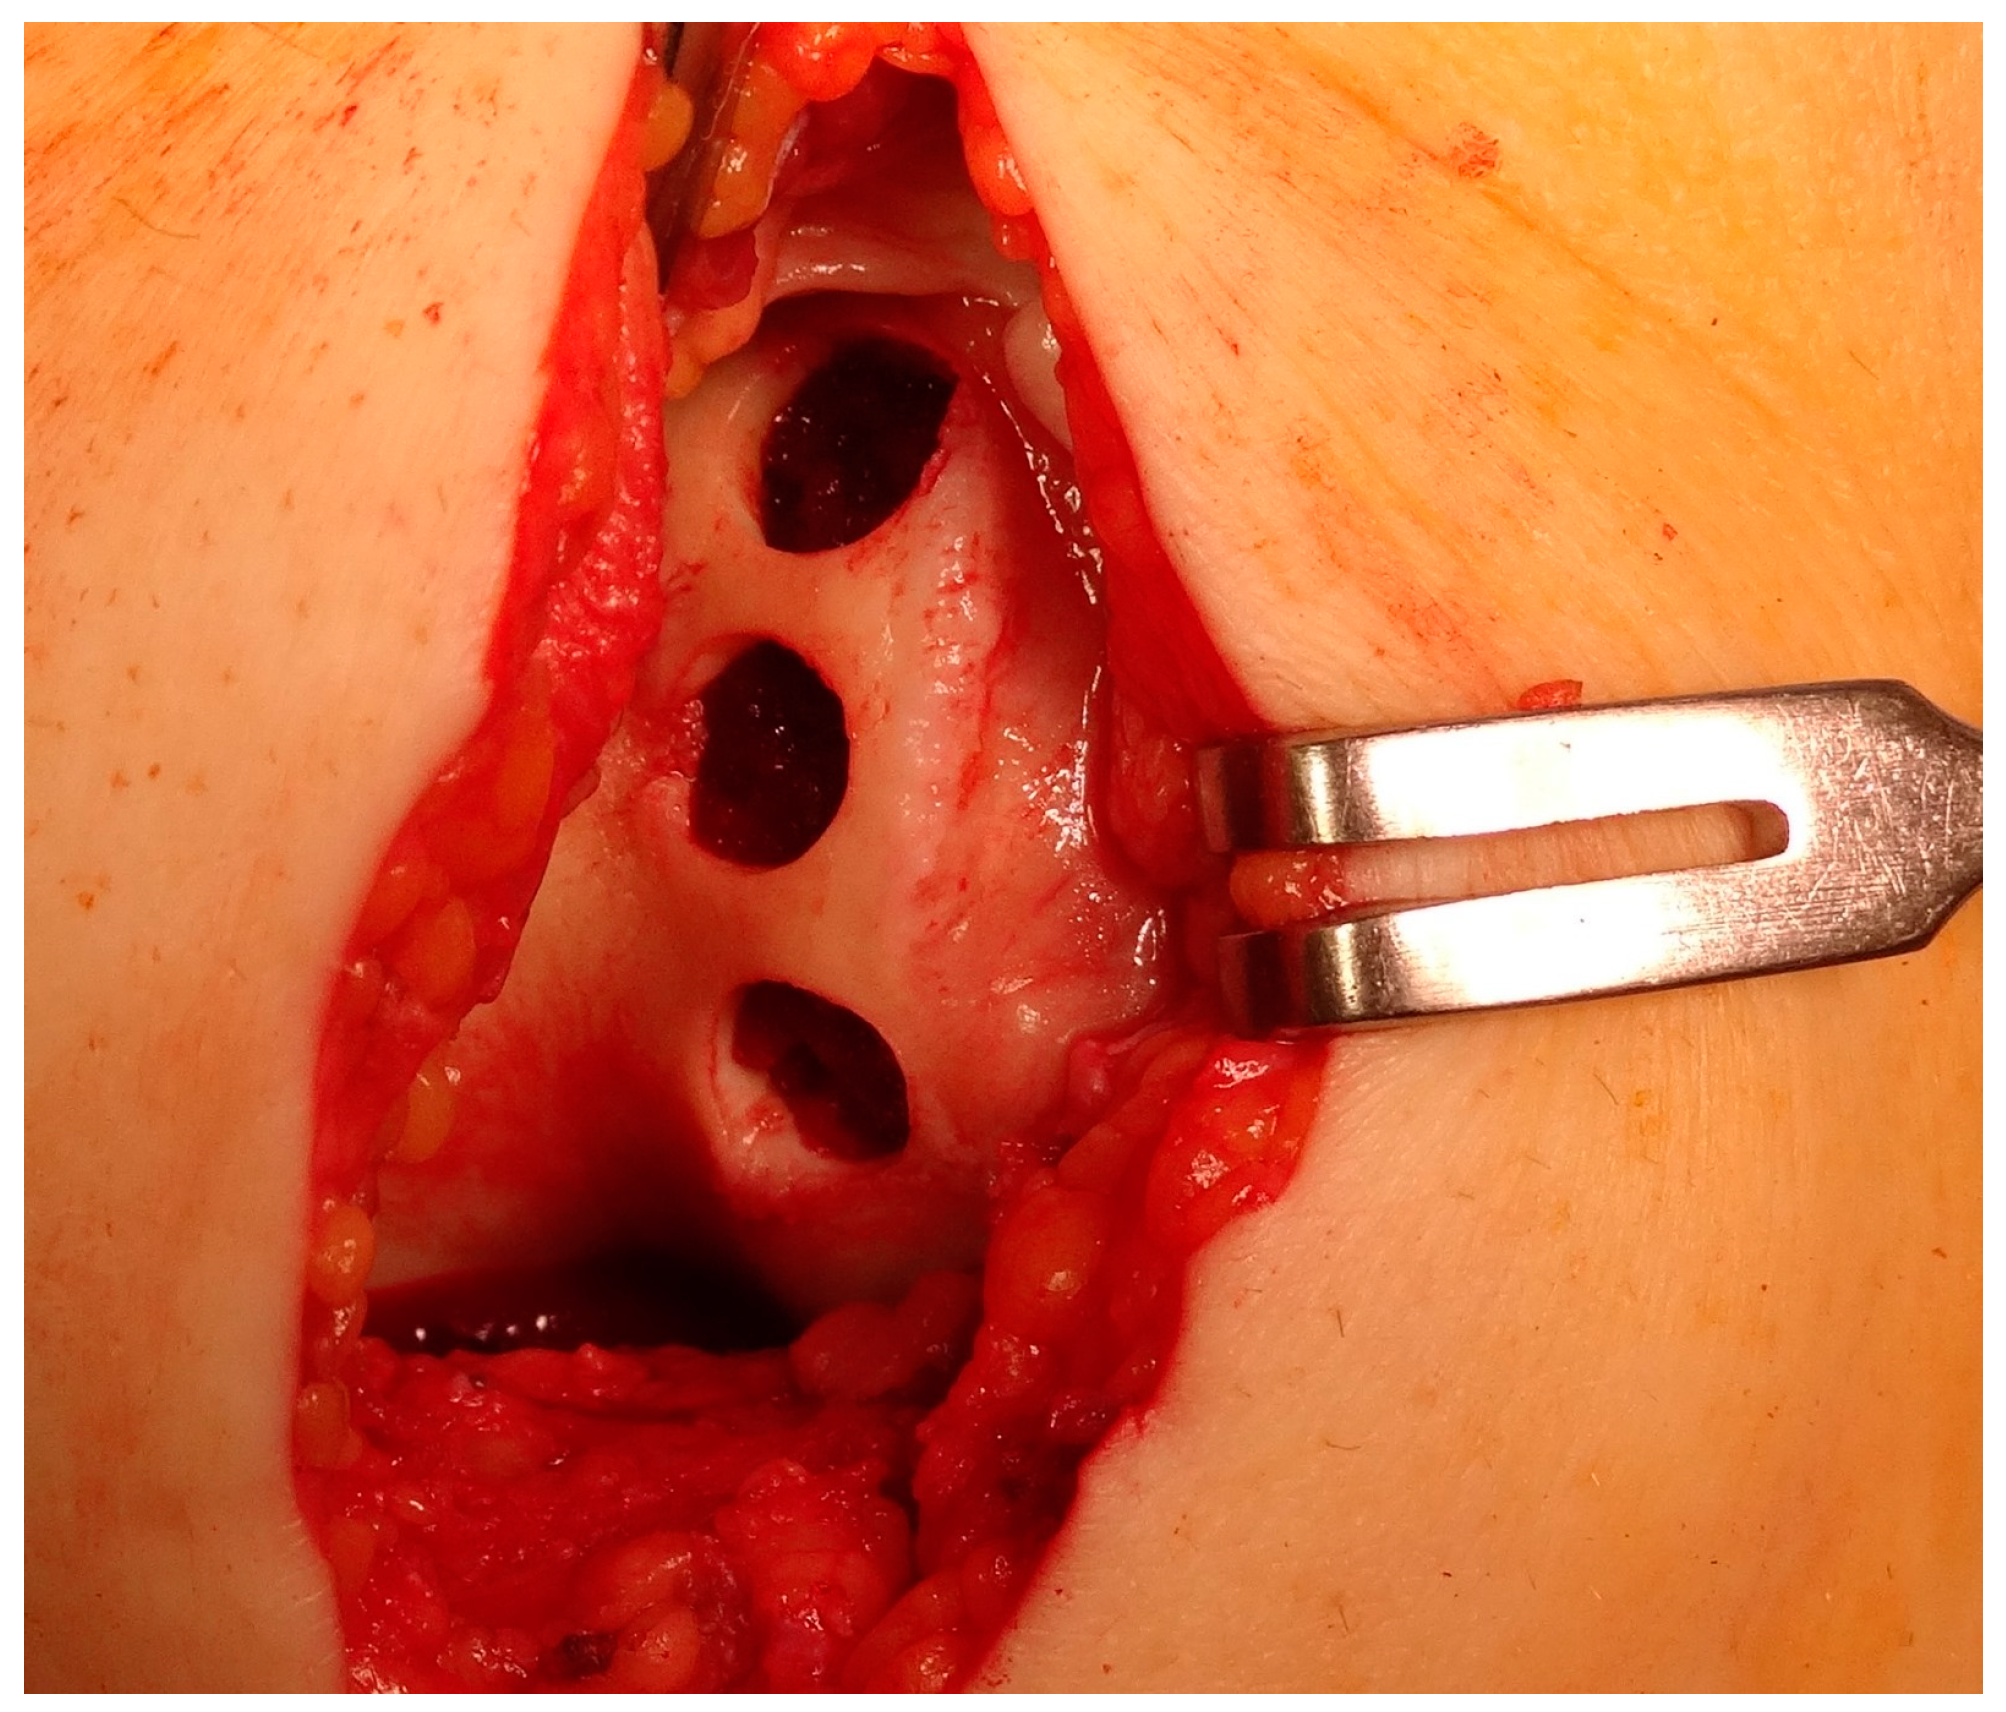

5.1. Microfracture